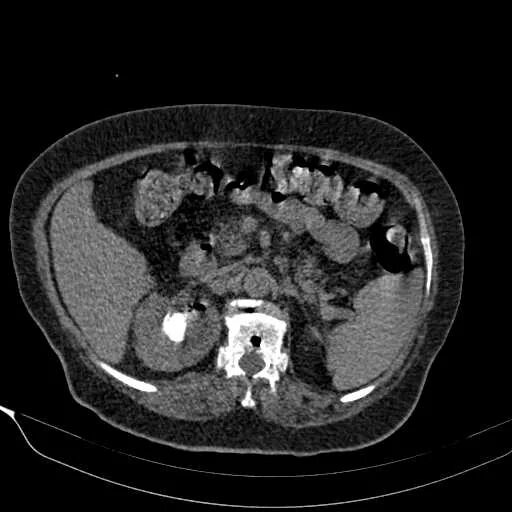

Пиелонефрит кт